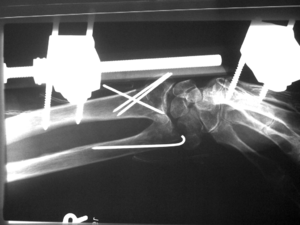

في 18 مارس 1924 أجرى كيرشنر أول عملية ناجحة لنزع السداد من الشريان الرئوي إنگليزية: pulmonary artery embolectomy، وهي العملية المسماة بـعملية ترندلنبورگ إنگليزية: Trendelenburg’s operation كما طور طريقة جديدة لعمل مريء اصطناعي، وطريقة لفتح مفصل الركبة جراحياً، أما الابتكار الذي خلد اسم كيرشنر إلى اليوم فهو أسلاك كيرشنر التي ما تزال تستخدم في جراحة العظام.